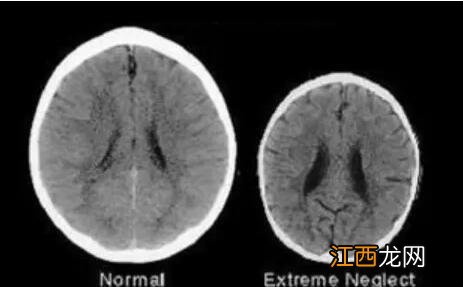

科学家们曾对2个3岁的孩子,一个孩子经常被夸,一个孩子经常被吼骂,同时对他们进行大脑扫描 。

扫描结果发现,经常被吼骂的孩子 , 大脑明显小了一圈,脑容量变小了,智力发育也受到了损伤 。

科学家们在研究中还发现,经常被父母吼骂的孩子,长大后言语智商平均只有112分,比没有遭受过父母吼骂的孩子,平均分低12分 。